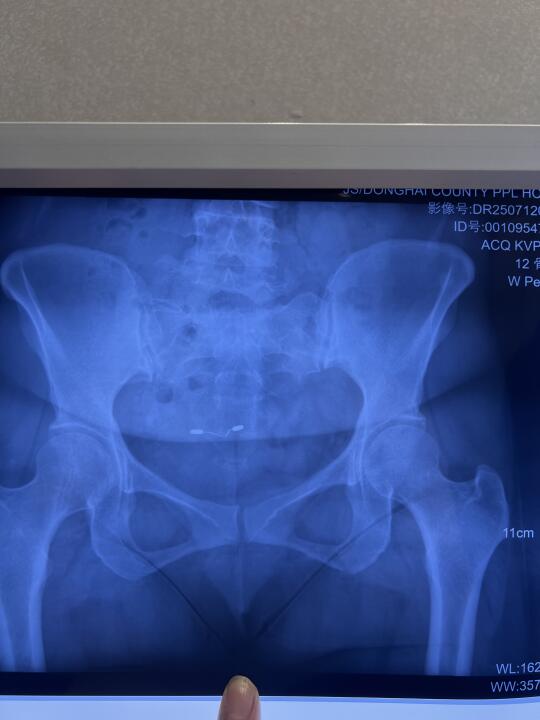

今天案主结束五天的矫正训练 昨天安排她今天上午去拍片子 从片子对比来看骨盆形态发生很大的变化 原来骨盆是长的 两个髂骨原来特别小 也就是左右髂前上棘都是内扣的 并且右边比左边扣得更厉害 现在两个髂骨形态上基本趋近正常 当然左右还有些差异 髂骨从小变大 说明左右髂骨相对于矫正前 向前旋了很多 另外注意看小转子到坐骨外侧的距离 矫正后的片子看明显距离大多了 说明坐骨比原来靠近了 再注意看股骨头顶在髋臼的位置 原来股骨头顶在髋臼偏上 矫正后股骨头顶的位置相对向下了 髂骨相对原来旋前所以她坐着腰就有力了 坐骨靠近后她感觉到坐骨把整个身体顶起来了 并且左右坐骨接近平衡了 能坐正了 原来坐不正 矫正前觉得右边坐骨硌左边没有支撑力 左右差异很大 之前走路腿迈不动要靠上身拽 腰胯腿都没有力 腰部是晃的 矫正后腰胯腿有力 走路腰不晃了而胯可以扭动了 能感觉到股骨头活动比原来丝滑多了 爬楼梯原来腿抬不起来 膝盖不舒服 现在爬楼梯股骨与膝关节都很轻松 能清晰地感觉到股骨头的滑动 人身上感觉少了几十斤 平躺的时候腰部悬空 矫正后腰能自然贴床 睡觉就觉得很放松与踏实 原来腰疼 骨盆周围疼 耻骨周围疼 腹股沟牵扯 尾椎疼 现在随着骨盆的调整身上各种痛症基本解除 还有就是原来中医说她是上热下寒 之前小腹臀部腰都是凉的而且会出凉汗 矫正后感觉骨盆区与腰腹和上半身的温度一样了 也不出凉汗了 因为她的骨盆极度后倾加向下掉 腹股沟挤压得非常厉害 股动脉一定压力大 所以血向下流不畅 骨盆与股骨头的角度变化后 腹股沟的空间打开些 自然股动脉的压力小了自然气血就通畅了 盆腔与下肢的温度自然提高了 其实很多中医诊断为上热下寒的问题的基本上骨盆与股关节都有问题